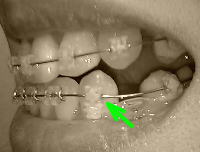

調整日までに1回ぐらいは更新しようと思っていたんですが、結局餅が上がらず…。というのも、やっぱり出っ歯状態が改善されるかどうか、ずっと不安で書く気にならなかったんですね。で、今回の調整にあたって、先生に聞いておきたいことをいろいろ考えましたが、やめました。結局こちらの希望としては、受け口だった下顎はきれいに引っ込んでるので、その下顎に合わせて上顎を引っ込めて、噛みあうようにしてほしいってことで、それはわざわざ言わなくても、当然先生だってそのつもりに決まっていることだし…と思って。インプラントの費用と、概要(何本打つかなど)については聞くつもりでした。それと、咀嚼するときに右側の上下7番の装置の間に頬の肉が挟まって痛い!のをなんとかしてもらいたい。さてドキドキしながら矯正歯科へ。まず下顎から。「右の抜歯跡も埋まりましたね。ただ、念のためあと1ヶ月はパワーチェーンで引っ張っておきます」ということで、引き続き3番→6番をパワーチェーンで。2本から1本にはなりました。捻じれてたのをブラケット付け替えとゴムで動かしていた左の3番も、かなりいい感じで並んできました。こちらはゴム→リガチャーに変更で、さらにぎゅっと引っ張り込んでいきます。来月には完璧になるでしょうか?ここで、右の上下7番の装置で頬の肉を噛んで痛い、と訴えてみました。「ああホントですね。装置をちょっと削って挟まないようにしましょう」と、削ってもらうことに。ガリガリガリガリゴリゴリゴリゴリ!!!ひいいいいい。怖い!すごい響くし!挟まなくなったかどうかは、ご飯時のお楽しみ。で、上顎です。「下顎がほぼ出来てきたので、今日は前回予告した通り、歯と歯の間を薄く削っていきます。余力を残しておきたいので、今日削るのは正中と1番と2番の間(左右)の3箇所、合計で1.5ミリ分を削ります」とうとうキタ━━━━━━(゜∀゜)━━━━━━ !!!!! 「すごくイヤな音がしますけど、我慢してくださいね。しみたりしたら言ってください」そういえば、歯を削られるのなんて何年ぶりだろう…。もう10年以上虫歯になってないからなぁ。すごいイヤな音がするらしいなぁ。と覚悟をしていたのですが、キュイーンと軽い音で、ぜんぜん平気でした。さっき装置を削った時に比べれば!!この隙間は、左右とも3番のフック→7番にパワーチェーンで前歯が奥に引っ込むように引っ張ります。どうか引っ込みますように!!帰り際、インプラントの費用について聞きました。「3万円と消費税です」「1本3万円ですか?」「いいえ、何本だろうが、必要本数ぜんぶで3万円です」ふーーーーん。思ってたより安い…。けど、今日は先生からインプラントの話はまったく出なかったなぁ。「現時点で、先生はインプラント必要だと思われますか?」と聞いてみました。すると、「今の時点では、必要ないと思います。ワイヤーのみで十分対応可能な程度だと思いますので」という答えで、「最後の最後で、もう一息パワーがほしい、という時に使うかもしれない、ぐらいに思っておいてください」と付け加えられました。ちょっと安心。次は1ヶ月後です。